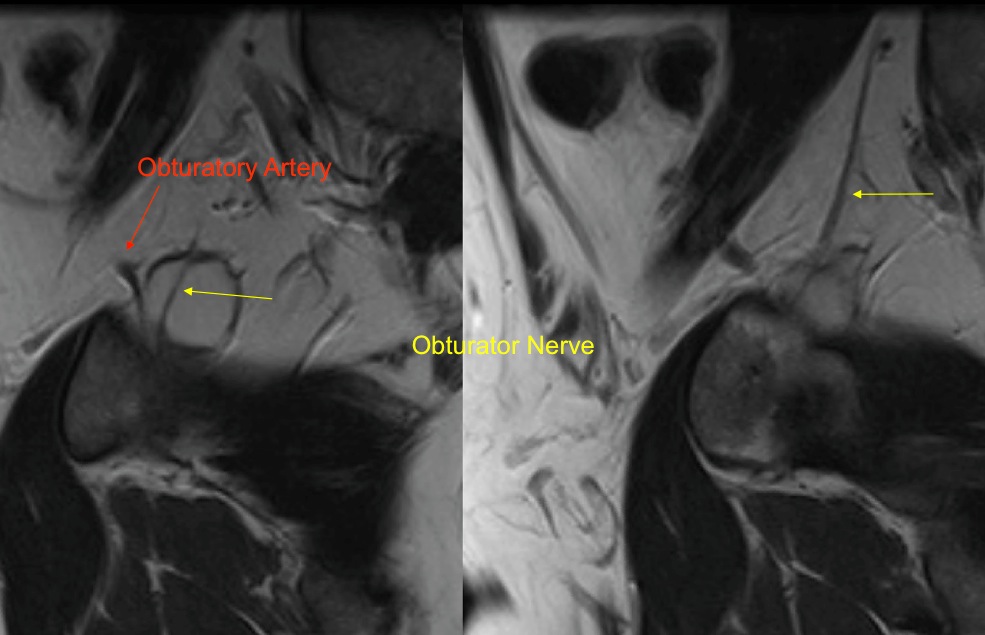

Figure 1 for case Obturator nerve impinge by ganglion cyst

Figure 1

Figure 2 for case Obturator nerve impinge by ganglion cyst

Figure 2